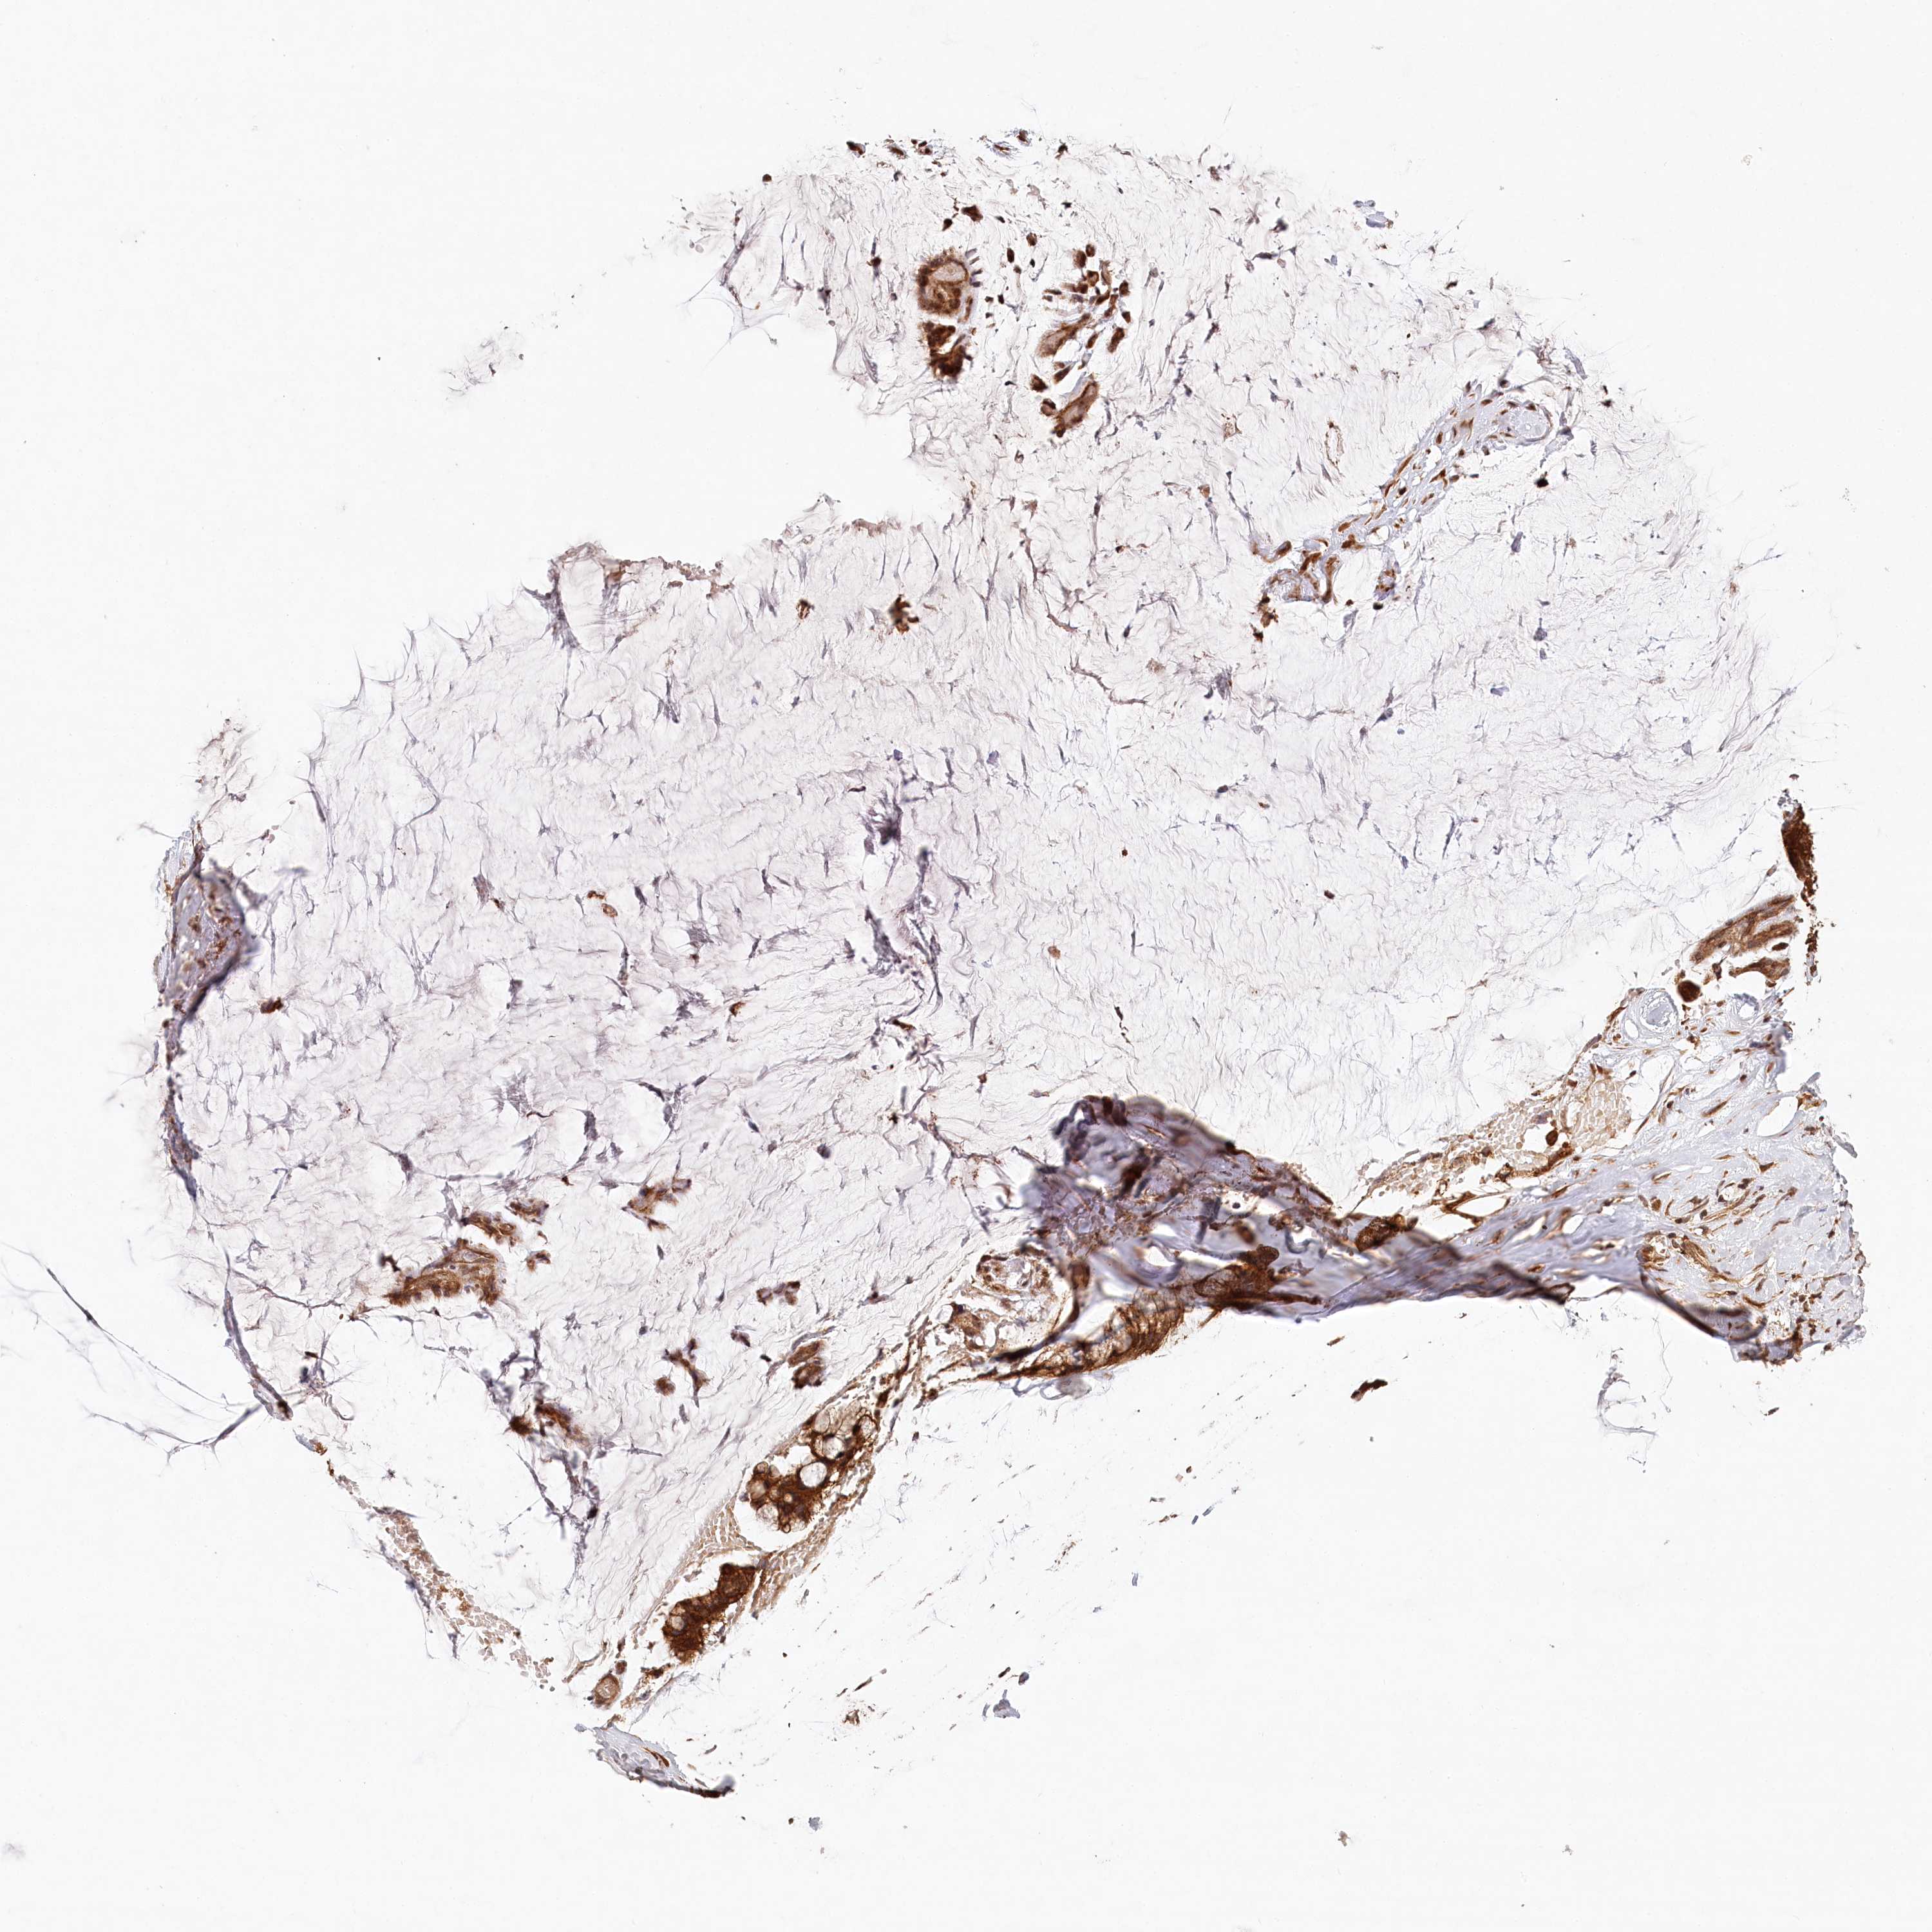

OVARIAN CANCER - Protein expressioni

A mouse-over function shows sample information and annotation data. Click on an image to view it in a full screen mode. Samples can be filtered based on level of antibody staining by selecting one or several of the following categories: high, medium, low and not detected. The assay and annotation is described here.

Note that samples used for immunohistochemistry by the Human Protein Atlas do not correspond to samples in the TCGA dataset.

Antibody stainingi

Antibody staining in the annotated cell types in the current human tissue is reported as not detected, low, medium, or high, based on conventional immunohistochemistry profiling in selected tissues. This score is based on the combination of the staining intensity and fraction of stained cells.

Each image is clickable and will lead to virtual microscopy that enables deeper exploration of all samples and also displays staining intensity scores, fraction scores and subcellular localization as well as patient and tissue information for each sample.

Antibody HPA032060

Antibody CAB034116

Staining

Not detected

Intensity

Negative

Location

None

Carcinoma, NOS